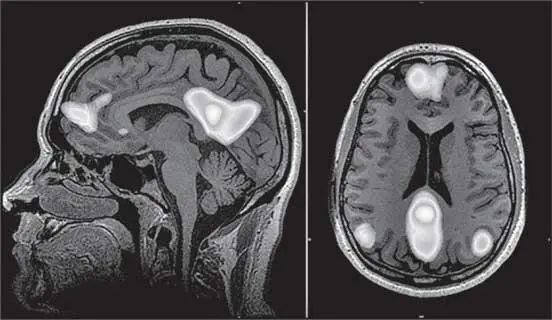

Выяснилось, что, когда мы решаем какие-то задачи, мозг снижает активность в следующих серверах обработки информации: медиальной префронтальной коре (благодаря ей мы понимаем других людей), латеральной теменной коре (отвечает за планирование сложных движений), задней части поясной извилины (помогает оценивать иерархию в обществе, сопротивляться мнению большинства), энторинальной коре (кодирует информацию о контексте, связанном с окружением) и других.

Дефолт-система мозга

В 2001 году Маркус Райхл сформулировал концепцию дефолт-системы мозга (ДСМ). На первый взгляд может показаться, что это как бы «система ничегонеделания», но это не так. Выяснилось, что, когда мы отвлекаемся от дела, мы отвлекаемся на что-то внутри себя. Оказалось, что ДСМ – это сеть, которая отвечает за наши рассуждения о социальных отношениях. Оцените, как часто вы думаете о взаимоотношениях с друзьями или родственниками? На самом деле мы все постоянно на это отвлекаемся: доволь-на ли моя вторая половина, не обидел ли я коллегу, почему со мной не разговаривает ребенок и так далее.

Рис. 40. Структуры дефолт-системы мозга (выделены светлым)

Вероятно, эта система, называемая также сетью пассивного режима работы мозга (СПРРМ), сформировалась в нашем далеком эволюционном прошлом, когда мы еще были стайными.

В те времена в небольших группах (120–150) особей наши предки боролись за выживание в жестоком мире. Им было важно держаться вместе. Поодиночке люди обычно погибали. Для того чтобы понимать все социальные взаимоотношения внутри стаи, у наших предков и сформировалась целая сеть – дефолт-система мозга. Исследования показывают, что наш мозг способен удерживать в активной памяти социальных взаимоотношений примерно 150 разных людей.